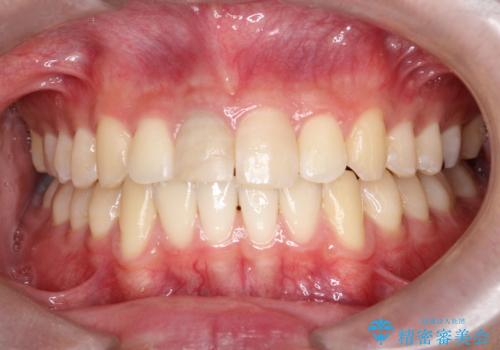

【ホワイトニング】右上前歯の歯茎の辺りが暗いのが気になる。

- 右上1番の色が暗いのを主訴に来院されました。

治療手順としましては、マイクロスコープ(歯科用顕微鏡)を使用し、元々入っていた詰め物のCR(プラスチック)を除去します。その後、歯の中に薬剤を入れ、蓋をします。2週間後に来院して頂き、白くなっているかを確認します。ご本人がご満足頂く白さになるまで、これを3~4回繰り返します。今回は1回で患者様がご満足されたので治療を終了しています。